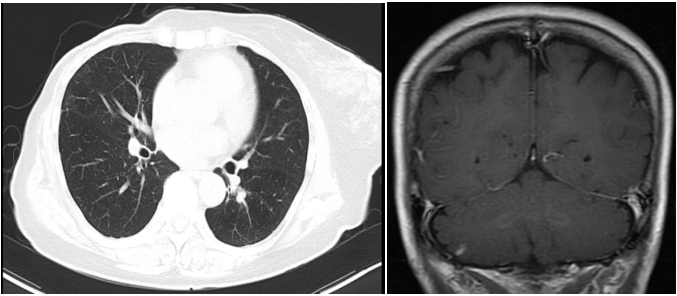

患者3年余前(2018.11)行右乳肿块穿刺活检,病理提示:右乳浸润性导管癌Ⅲ级,Ki-67(40%,+),ER(-),PR(-),HER2(3+)。PET-CT提示:右乳占位,考虑乳癌可能,伴右侧腋窝淋巴结转移,两肺及肝左叶多发转移,胸腰椎多发骨转移。头颅MRI未见异常。基因检测:ERBB2 基因拷贝数扩增。

图1. 2018.11肝左叶转移灶

图2. 2019.01两肺转移灶

两个疗程后复查CT:右乳Ca伴右腋下淋巴结M(较前相仿),伴两肺弥漫性转移(图3,较前缓解),肝脏转移灶消失(图3)。胸腰椎转移灶,较前相仿。疗效评价PR。

图3. 2019.03两肺转移灶(左图),肝左叶转移灶(右图)